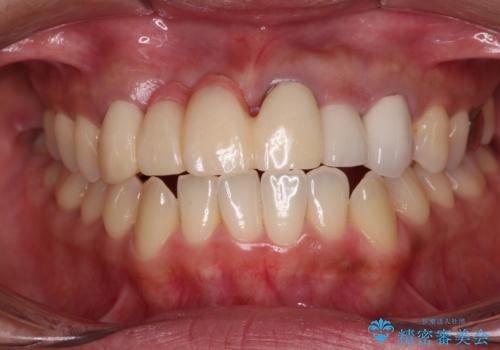

- 前歯を2本抜歯した後に装着した仮歯が長く見えるのが気になるとのことで来院された患者様です。

抜歯後には歯を支えていた骨が失われるため、歯肉が痩せてしまい、結果としてブリッジのダミーの歯を長くする必要があります。

前医では、歯肉の位置に相当する部分を、歯肉に近い色とすることで歯の長さが揃っているようにカムフラージュする治療が提案され、仮歯もそのようになっていました。